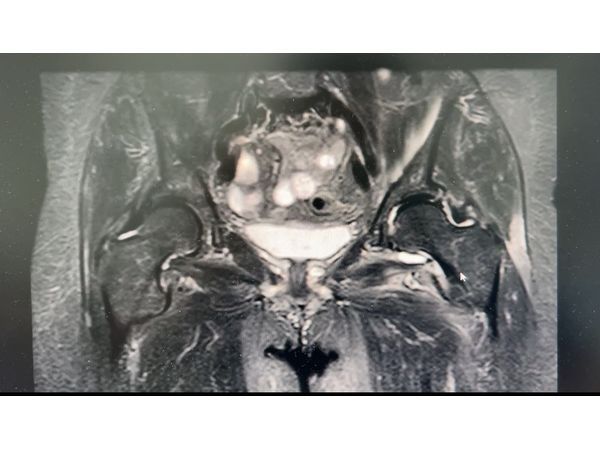

На МРТ в проекции тазобедренного сустава обнаружили пирофосфатные отложения с признаками воспаления мягких тканей, отёк и двухсторонний коксартроз I степени. Также выявили слабый синовит левого тазобедренного сустава. Суставные поверхности в норме.